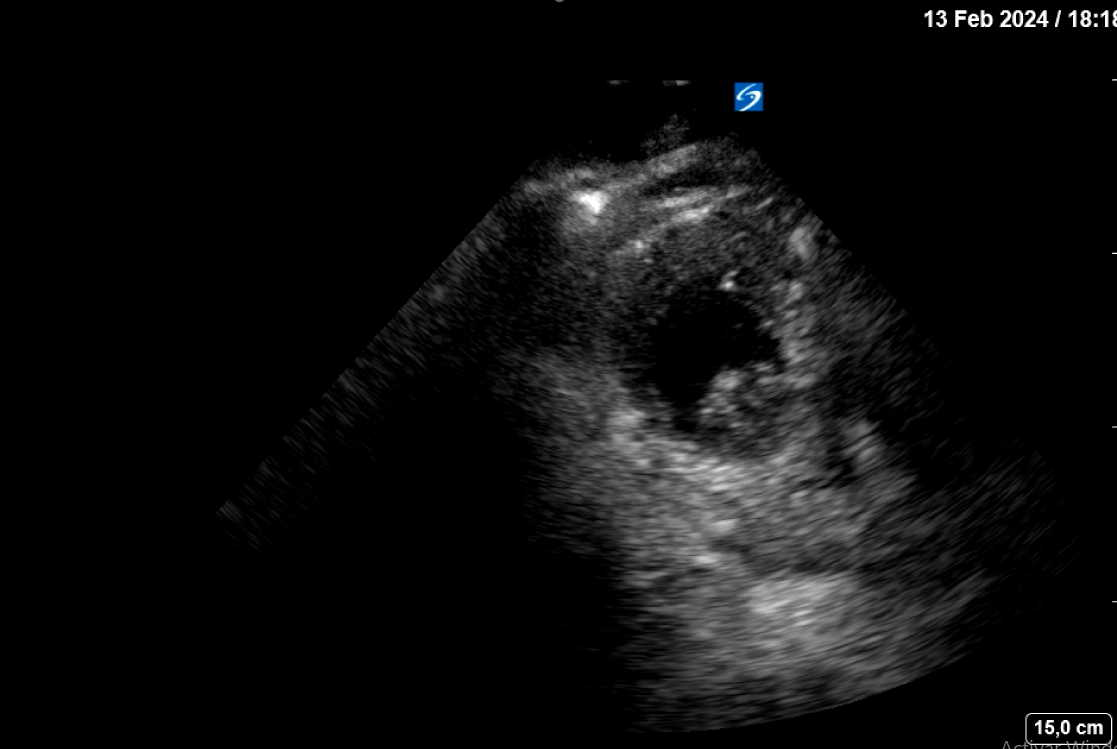

La estabilización hemodinámica junto a los parámetros clínico-ecográficos indican un taponamiento fibrinoso de la rotura cardíaca. Se decide ingreso en planta de medicina interna tras pico de troponina de 7000 pg/mL con el diagnóstico rotura cardíaca contenida. A las 10 horas de la 2ª ecografía clínica y antes de su traslado a una planta médica, se realiza una tercera ecografía clínica dirigida estando el paciente consciente, estable sin dolor. En el mismo se aprecia el mismo derrame pericárdico moderado idéntico al objetivado previamente, pero hay un nuevo hallazgo en el ápex del VI: un trombo intracavitario adherido (imagen 2).